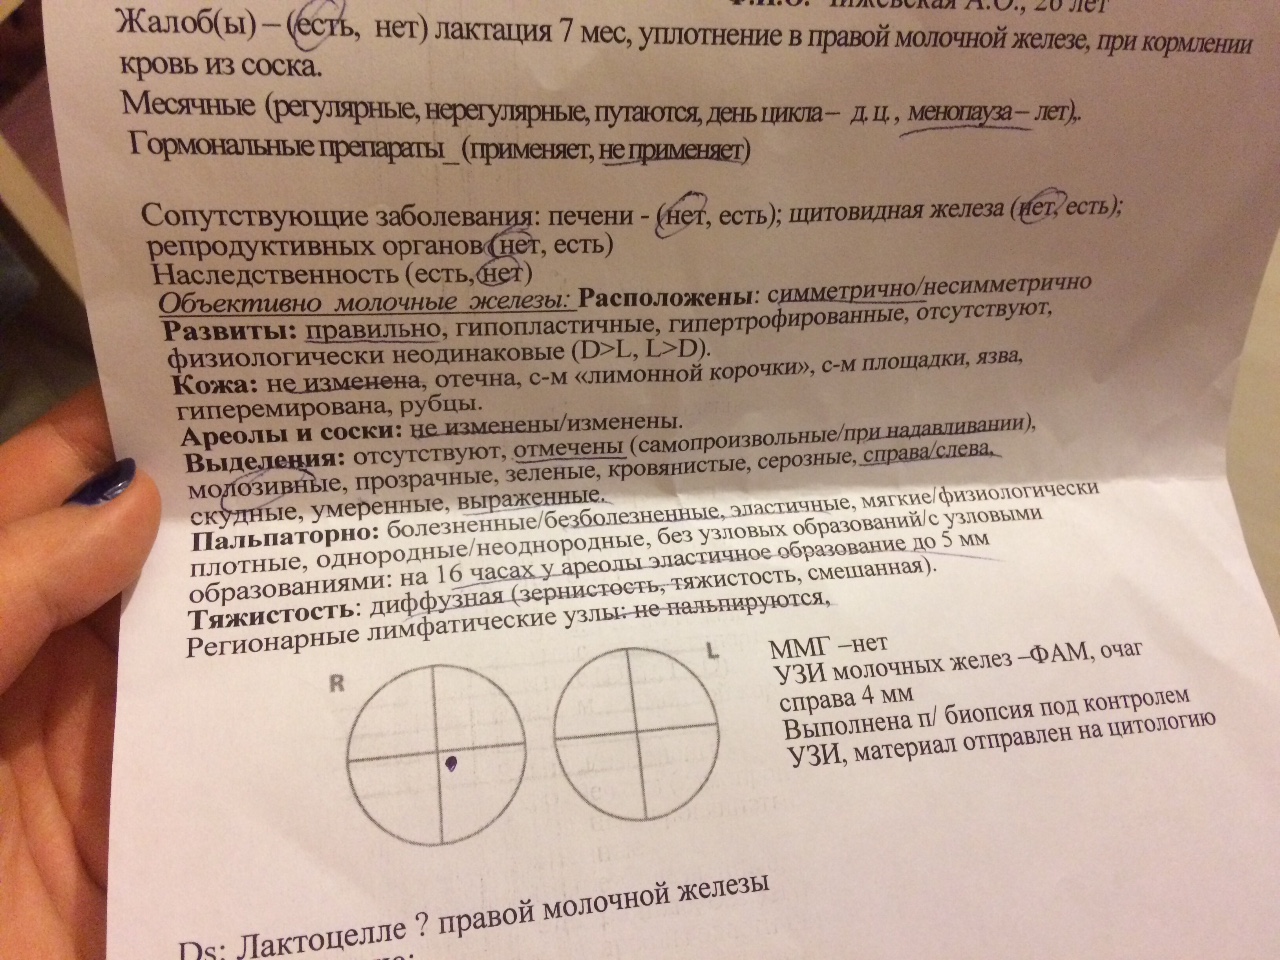

Обратитесь к врачу для точной диагностики и исключения злокачественных образований.

Следуйте рекомендациям врача по дополнительным обследованиям, таким как УЗИ или маммография.

Уплотнения в молочной железе. Что делать?

Уплотнение в молочной железе, киста или узелок в груди, что делать.